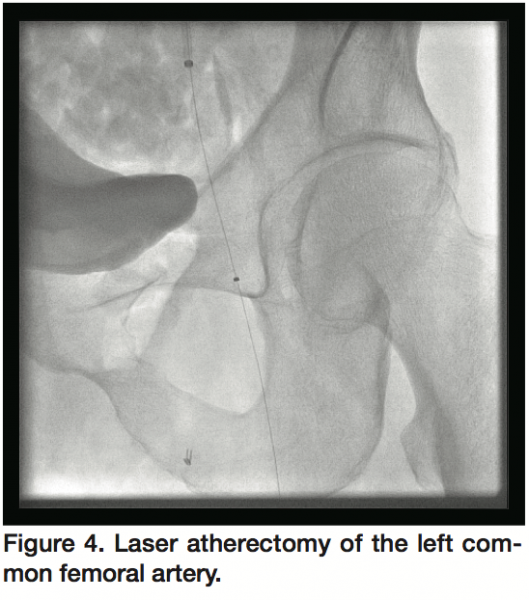

Access was obtained in the right common femoral artery and selective left external iliac artery angiogram was performed, which confirmed hazy thrombotic occlusion of the left common femoral artery at the site of AngioSeal (St. Jude) deployment with reconstitution at the bifurcation of the left superficial femoral and profunda femoris arteries (Figure 2). With the support of a 4 Fr glide catheter, an angled Glidewire (Terumo Medical) was used to cross the occlusion into the distal superficial femoral artery (SFA) with a gradient of 50 mmHg across the occlusion. Rheolytic thrombectomy was then performed using an AngioJet catheter (Medrad Interventional) with multiple runs into the SFA (Figure 3) and profunda femoris artery with improvement in flow across the lesion but persistence of residual thrombus. The glidewire was then exchanged for a Confianza Pro 0.014 mm wire (Asahi Intecc) and laser atherectomy was performed using a 1.7 mm Turbo Elite laser catheter (Spectranetics) utilizing fluence/rate settings of 40/40, 60/60, and 60/80 serially (Figure 4) with further improvement of flow across the left common femoral artery.